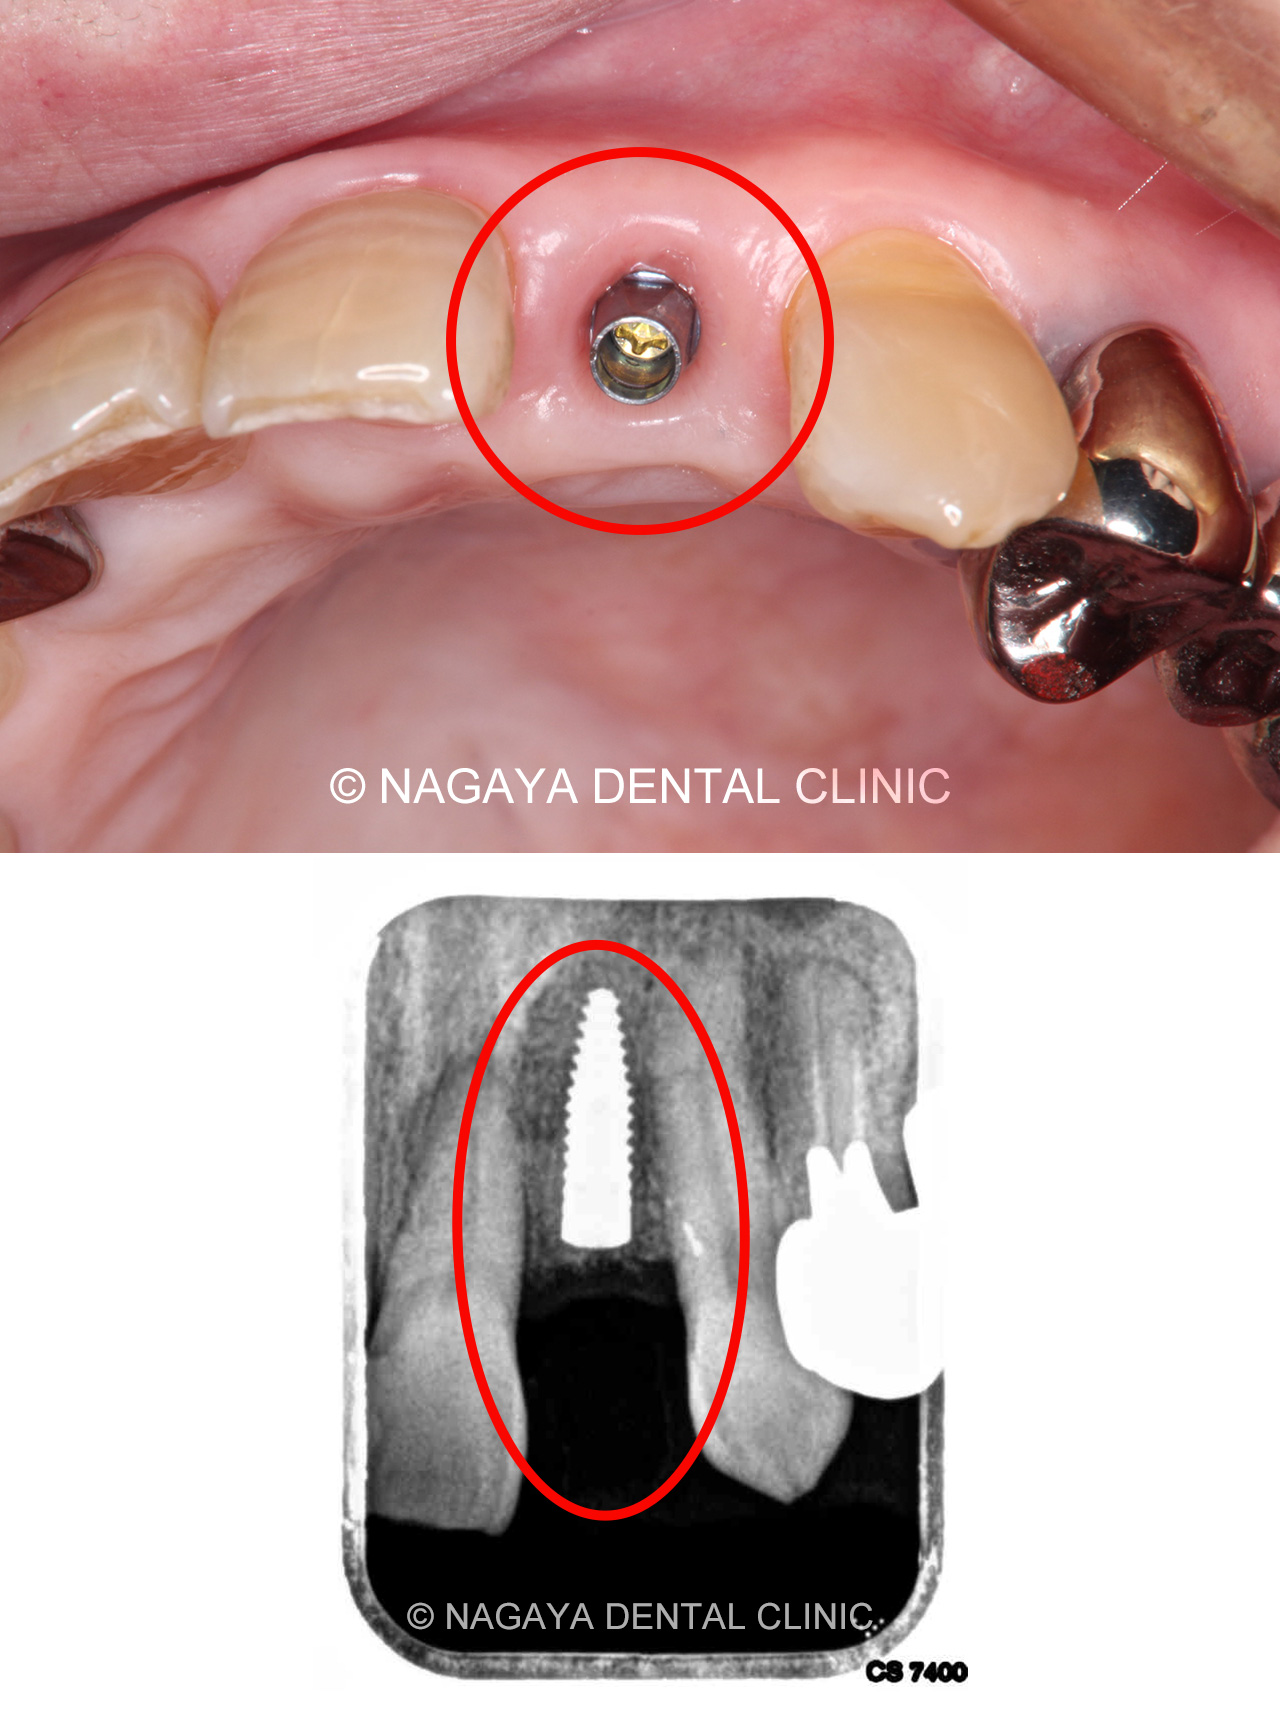

| 主訴 | 時々腫れる |

| 治療方法 | インプラント |

| 治療の説明 | 歯根が破折していた為、診断の結果抜歯が必要となりました。 患者様のご希望で、歯のない部分はインプラントによる治療を行いました。 クラウン(被せ物)は、ジルコニアセラミックスを選択された為、より天然の歯に近い形になりました。 |

| 治療期間 | 8ヵ月 |

| 副作用(リスク) | インプラント手術後は、出血、腫れなどがおきる場合がありますが、時間経過とともに治癒します。 また、喫煙、糖尿病、加齢、清掃不良などに伴いインプラント周囲の骨に炎症が起こり、再治療が必要になるケースがあります。 |